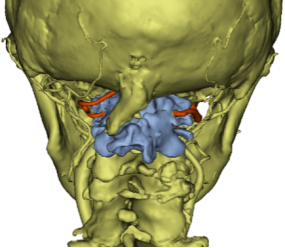

骨科主任、脊柱外科主任沈洪兴组织了详尽的术前讨论,并与手术室、麻醉科、重症监护室等多科室紧密合作,共同为陈阿婆制定了一份周密的手术计划:先进行为期一周的术前颅骨牵引准备,再进行手术复位。在沈洪兴主任的指导下,手术由朱超主刀,使用大重量牵引技术,向上推开椎动脉,巧妙翘拨复位寰枢关节,并借助机器人辅助导航系统,精准植入固定装置,既实现了寰枢关节的精确复位,又保护了椎动脉和脊髓神经。

术后,陈阿婆的肢体麻木感显著减轻,精细运动能力也逐步恢复。影像学检查结果显示,陈阿婆的椎管直径增加了超过一倍。得益于细致的术后护理和系统的康复训练,术后两个月返院复查,陈阿婆已恢复独自行走,双手灵活性也大大提升,生活质量显著提高。

术后寰枢关节复位,椎管通畅